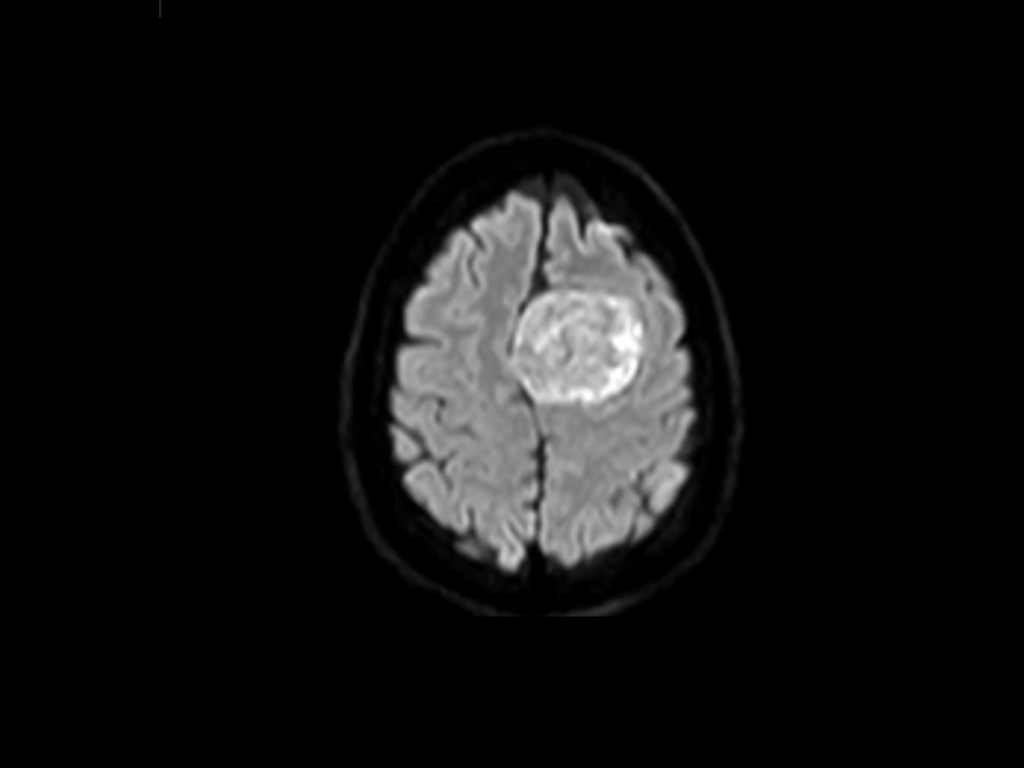

Her mother, Laura Hooten, rushed her to Baptist Hospital, where a CT scan revealed a mass on the frontal lobe of her brain.

Days later, she explained that the tumor was thankfully benign and non cancerous. It was a grade one meningioma, and the final measurement was 7 cm.